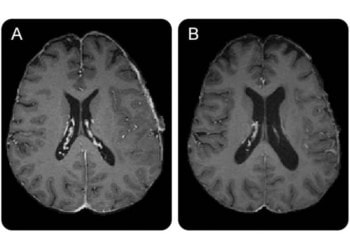

Read moreDetailsHow does the cross-talk between brain networks change when working memory - the mental assembly of information needed to carry...